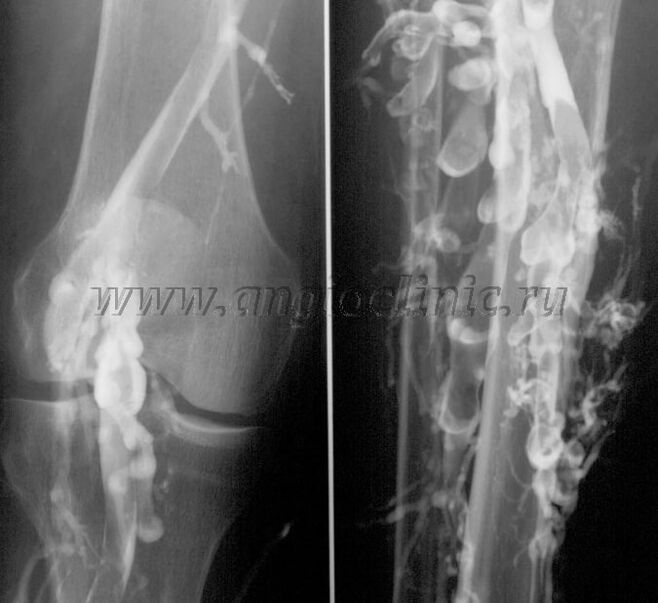

Kontrastna venografija

Običajno je ultrazvočno skeniranje dovolj za popolno diagnozo venske patologije, vendar je v nekaterih primerih potrebno preučiti razmerje med stanjem globokega in površinskega venskega sistema, zlasti v primeru recidivov krčnih žil in sekundarnih krčnih žil.

Za rešitev teh težav se uporablja kontrastni rentgenski pregled. Saphenous vene punktiramo in damo kontrast. Na monitorju rentgenskega aparata opazujemo gibanje kontrasta in izvajamo vse potrebne teste in projekcije. Trenutno se venografija za krčne žile uporablja zelo redko.